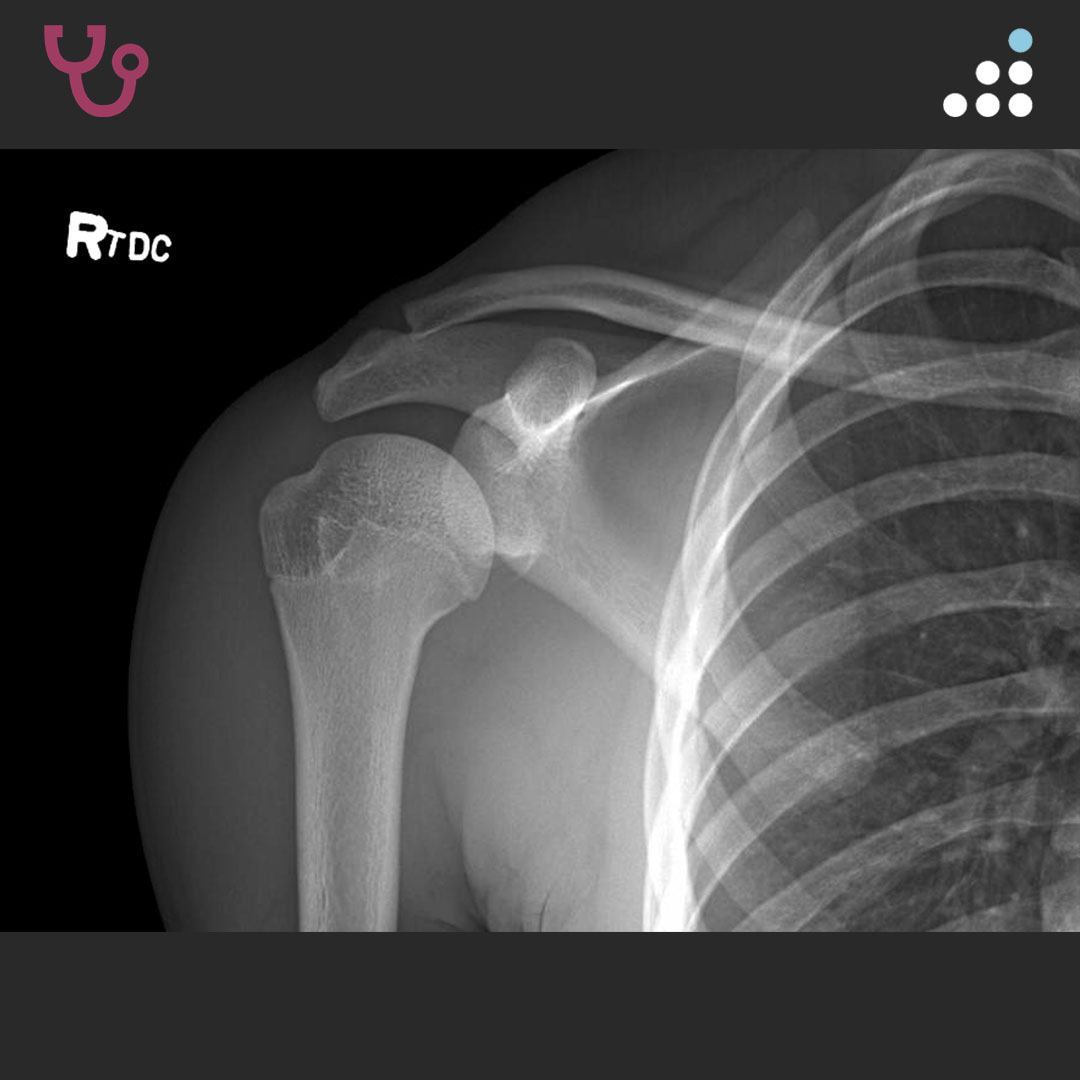

HPI: This is an 18-year-old male who sustained a right shoulder dislocation during a football game on 11/2018. He subsequently had a repeat dislocation in his sleep one week later, which was reduced in the ER. Since then, he has had approximately 7-9 instability events, none requiring formal reduction. He is a senior in high school and desires to play football as soon as he can, with plans to walk on in college.

PMH: Past medical history significant for eczema and sickle cell trait.

PE: On exam, the patient fires deltoid in all three planes. He has full PROM and full 5/5 RTC strength. There is positive subacromial tenderness, negative neer/Hawkins, and no TTP along the biceps tendon. He has a 2+ anterior load shift with guarding and a 1+ posterior load shift. There is pain but no apprehension in all degrees of abduction/ER. He has a negative Obrien’s test and normal resting scapular motion.

SHOULDER INSTABILITY IN 18M